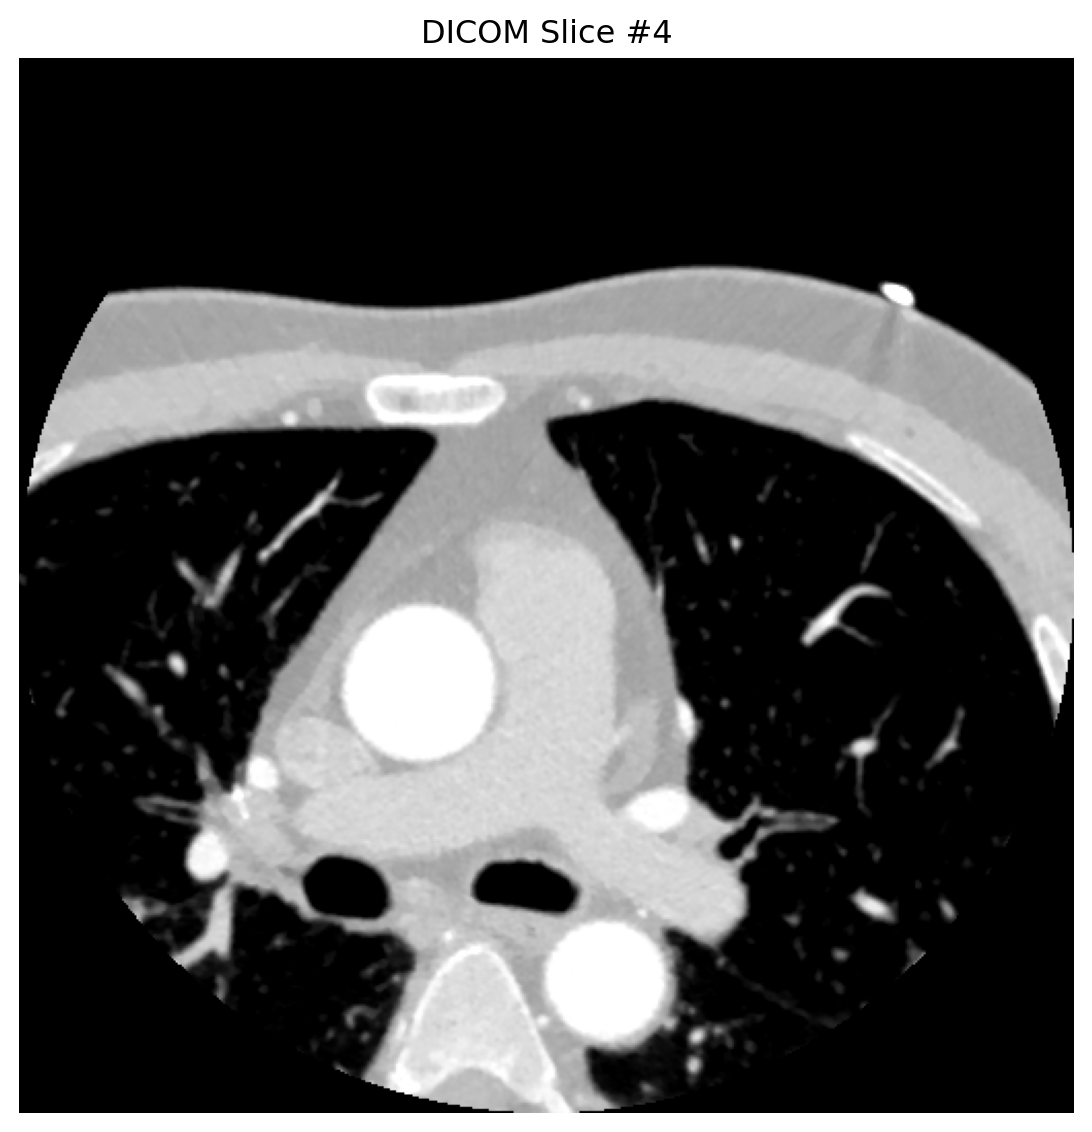

# 分析多个代表性切片

for slice_idx in [0, 4, 8]:

dataset = analyze_dicom_slice(slice_idx)